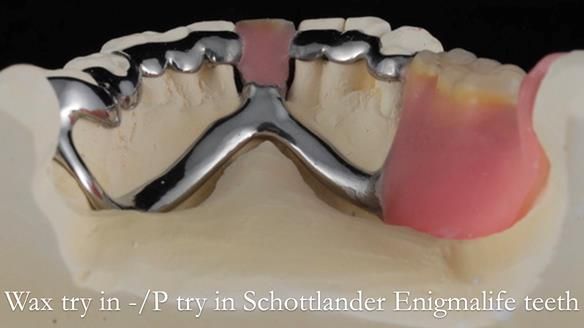

Welcome to my Newsletter 54 showing the making and fitting of dentures (a complete upper metal reinforced denture, a lower immediate partial denture and a definitive Scandinavian designed, metal based lower partial denture) for David, a 75 -year-old man. The full protocol workflow is presented including the use of dentate photographs to mimic his natural teeth.

Interestingly we found that the upper complete denture when finished and fitted didn’t have good enough retention for David’s satisfaction. It was relined by adding compound to the buccal flanges – to almost overextend into the sulcus to ‘create’ a sulcus, followed by using a light bodied silicone impression material. This improved the function of the C/-considerably. A lower Scandinavian hygienically designed lower RPD was also provided which helped with occlusal stability and reseating the upper denture – further improving the fit.